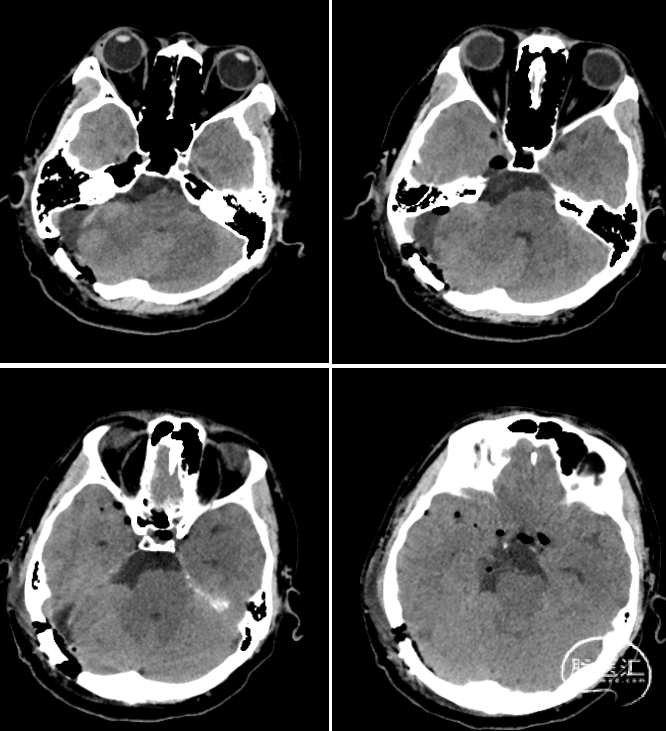

术后CT